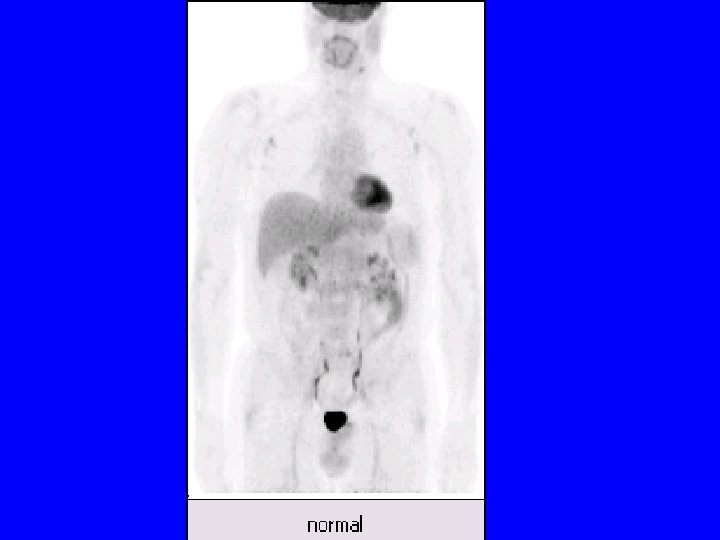

Réalisation technique • • Le patient à jeun et au repos FDG injecté en IV Durée examen # 40 min Acquisition « corps entier » Reconstruction des images Visualisation coupes / 3 plans Corps entier en transparence Calcul éventuel du SUV

TEP • Tomographie par Emission de Positons – imagerie fonctionnelle ou métabolique – substance radioactive émettrice photons gamma – Médecine Nucléaire • PET : terme anglo-saxon – Positron Emission Tomography